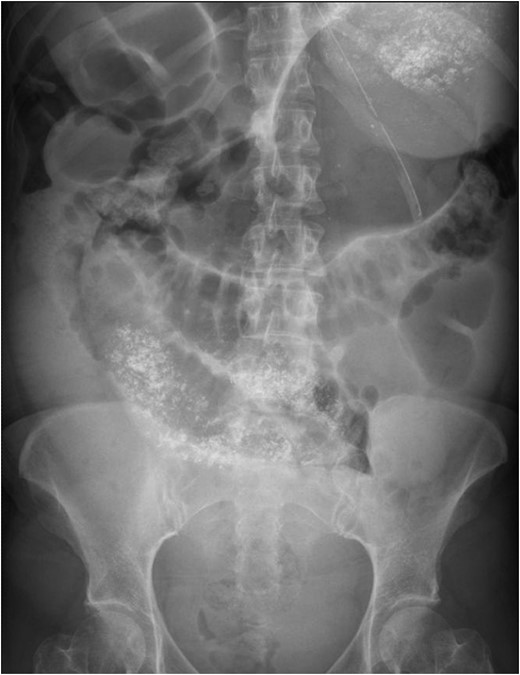

A healthy 41-year-old female, 38-week pregnant, presented with irretractable abdominal pain and vomiting. There was no previous similar history or abdominal surgery. She associated the onset of symptoms with a low energy fall on to her buttocks. There was no improvement despite hastening her elective caesarean section. Thereafter, she was treated as a post-operative ileus (Fig. 1). On multiple examinations, she remained afebrile and haemodynamically stable. The abdomen was distended, with generalized mild tenderness. Bowel sounds were audible. Blood tests were unremarkable. Failure to progress prompted further evaluation with CT. This revealed a small bowel obstruction secondary to a right-sided diaphragmatic hernia (Fig. 2). After resuscitation, she proceeded to laparoscopy.